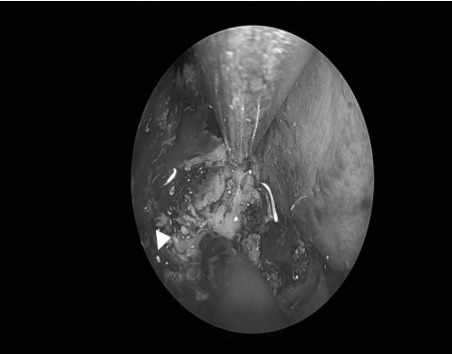

耳内镜检查:分泌性中耳炎(右)

双耳鼓膜完整,右侧鼓膜内陷明显,右侧鼓室可见积液